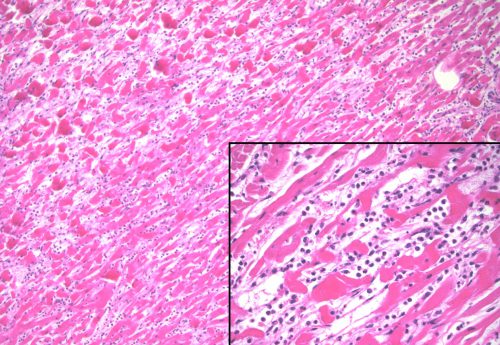

Ambii adolescenți au avut tablouri clinice similare, fără simptome cardiace evidente. Histopatologia lor nu demonstrează existența unei miocardite tipice. În acele cazuri, se pot constata infiltrate limfocitare (sau celule gigantice) cu necroză a miocitelor adiacente; modificări precum miocitele hipereozinofile și benzile de contracție sunt absente. În aceste două cazuri post-vaccinare, apar zone cu benzi de contracție și miocite hipereozinofile diferite de inflamație. Acest tip de leziune este în schimb similar cu ceea ce se observă în miocardul pacienților care sunt diagnosticați clinic cu cardiomiopatie Takotsubo, toxică sau „de stres”, care este o leziune miocardică temporară care se poate dezvolta la pacienții cu factori de stres extrem fizic, chimic sau uneori emoțional.[24-31]

Imagine dramatică – sângele copiilor decedați văzut la microscop (mai multe imagini în documentul din link-ul de mai sus):